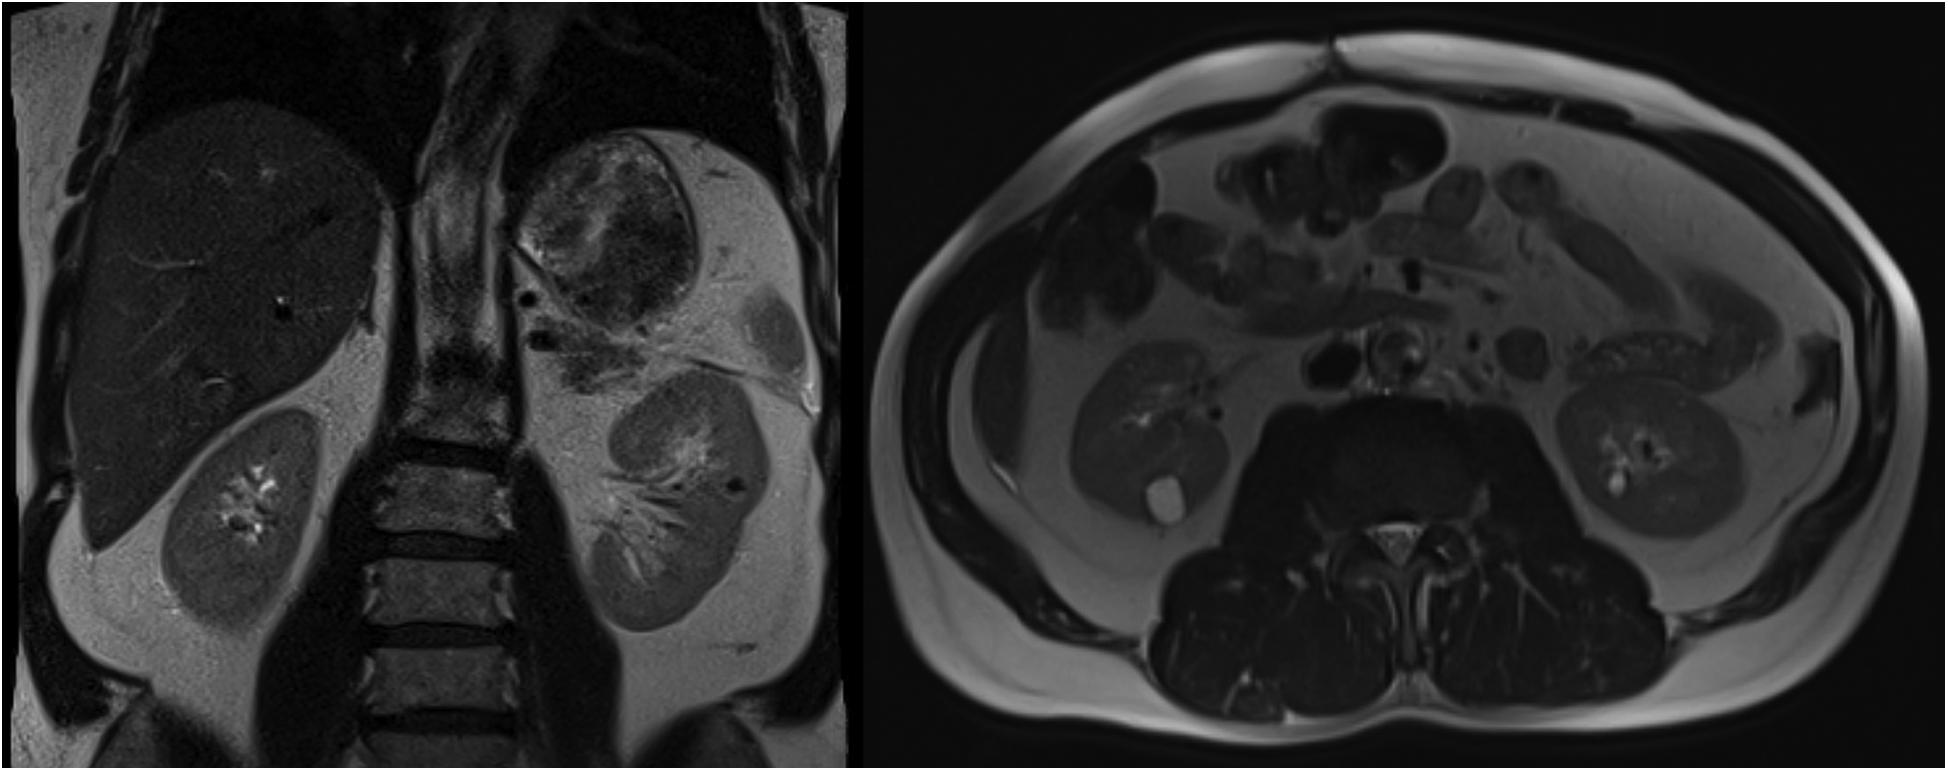

The patient's urine metanephrine and normetanephrine levels returned to normal. The patient complained of dizziness when standing up during postoperative in-hospital follow-up. In the etiological evaluation of orthostatic dizziness, we did not detect anemia, thyroid dysfunction, renal failure, and electrolyte disturbances. There was no dehydration. Adrenal insufficiency was not detected with cortisol levels and ACTH stimulation test (Table 1). Plasma renin activity and aldosterone values were normal (Table 1). Cardiac functions were detected as normal according to ECG and TTE. Tilt test was not performed because it was not tolerable. After discharge, the patient's complaint of severe orthostatic dizziness continued for two months. The average 24-hour ABP was 102/61 mm Hg at the first-month follow-up. Severe orthostatic dizziness was managed with a non-pharmacologic approach, which included increasing salt and fluid intake, modifying dietary habits, isometric exercises, and other lifestyle changes. Despite all this, the patient's mobility was severely restricted. The patient developed deep vein thrombosis in the left lower extremity. Orthostatic dizziness gradually improved after the second month without medical treatment. The average 24 h ABP was 122/69 at six months. The successful result in the control magnetic resonance imaging at one year is shown in Figure 2.

Figure 2

Magnetic resonance images at 1 year postoperatively showing successful resection of a giant cystic pheochromocytoma.